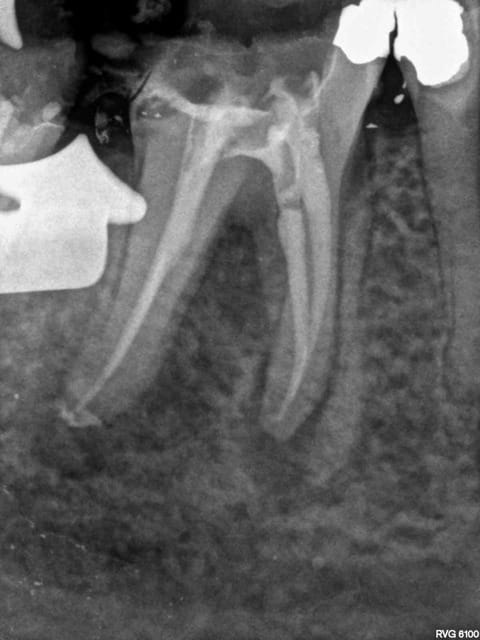

J'y travaille pour trouver un moyen simple et efficace pour poser la digue dans toutes les situations comme celle ci dessous. Tiens c'est tout frais, endo sc33 en 1 temps, 1H 15 et encore je n'ai pas d'assistante au fauteuil.

Technique "Monocône"....C'est un peu "has been" je trouve.... ;-)

Surtout mono-cone sans ciment. mais c'est vrai que quand on ne fait pas d'essayage de cones on ne risque pas de voir pas la différence.-))))

Mais je ne me cache pas que je les scelle de temps en temps. Mais manque de bol pas là. Thermo compactés au mac spaden. Tu vois peut être la différence non ?